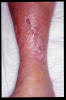

Insuficiencia venosa crónica